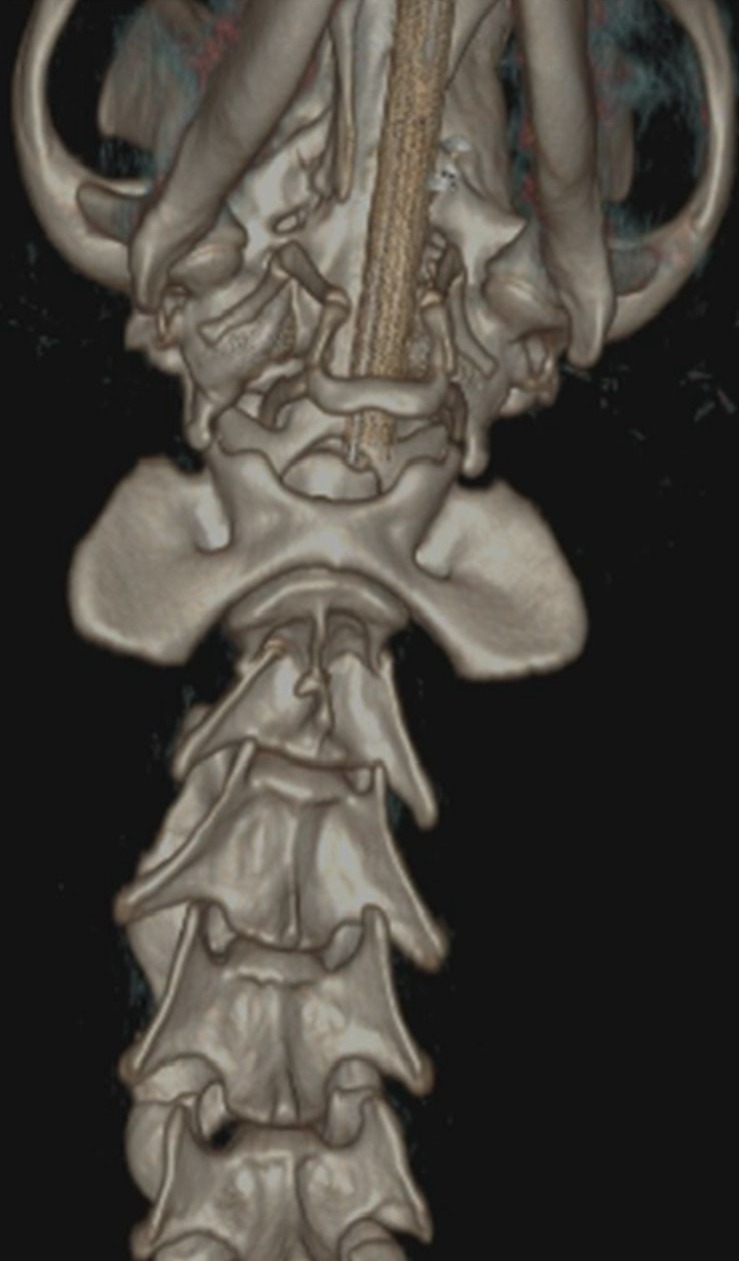

In a remarkable milestone for veterinary medicine, the neurosurgery team at CGS Hospital, led by Dr. Vikash Singh Chauhan, successfully repaired a cervical vertebra (C2) fracture using screws and PMMA.

A thorough neurological examination followed by a CT scan revealed a C2 vertebral fracture with severe spinal cord compression along with a scapular fracture. Woody also experienced intense pain when flexing his neck. Given the risk of permanent damage, the surgical team decided to proceed with an advanced spinal fixation procedure using screws and PMMA.